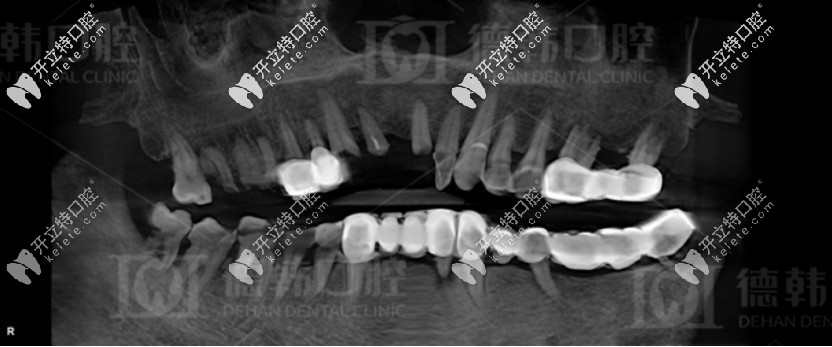

種植前爺爺?shù)难榔?/strong>

張?jiān)洪L(zhǎng)針對(duì)爺爺年齡大、口腔條件不佳的情況,為其制定了一套即拔即種的全口種植方案:總共種植了13顆種植體,其中下頜種植7顆種植體,十五天后再種植上半口,上頜種植了6顆種植體。